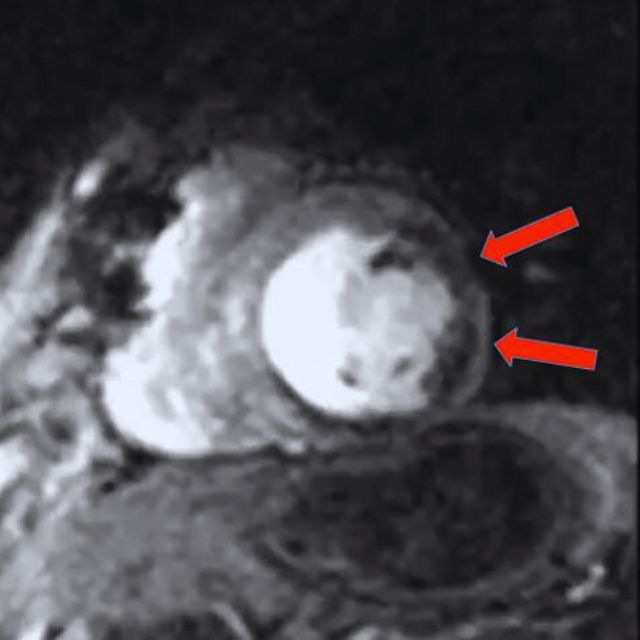

- Tissue Characterization (บอกสภาพเนื้อเยื่อ):นี่คือจุดแข็งที่สุด MRI สามารถแยกได้เลยว่า กล้ามเนื้อหัวใจของคุณหนาเพราะความดันโลหิตสูง, เพราะโรคพันธุกรรม, หรือเพราะมีพังผืด (Scar) จากการขาดเลือดในอดีต

⭐⭐⭐ ชัดเจนที่สุด |